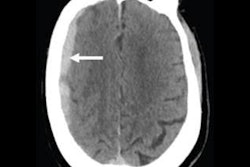

To assess the value of a 24/7 radiology service, Jalal and colleagues examined approximately 6,000 head CT scans of patients who presented to the hospital with head trauma before the service began (from March to September 2013) and after it was implemented (from September 2014 to March 2015). The pre- and post-24/7 radiologist coverage patient populations had comparable age and gender distributions.

The researchers calculated the amount of time that passed between when a head CT exam was acquired and initially interpreted (turnaround time 1), as well as the time between when the radiology report was transcribed and finalized (turnaround time 2).

When they compared the periods, they found statistically significant reductions in both categories of turnaround time after the implementation of 24/7 onsite staff radiologist coverage for the emergency department (p < 0.0001). These differences applied to men and women across all age groups.

| Head CT interpretation turnaround time | 9 hours, 38 minutes | 54 minutes |

| Head CT final report turnaround time | 26 hours, 17 minutes | 2 hours, 1 minute |